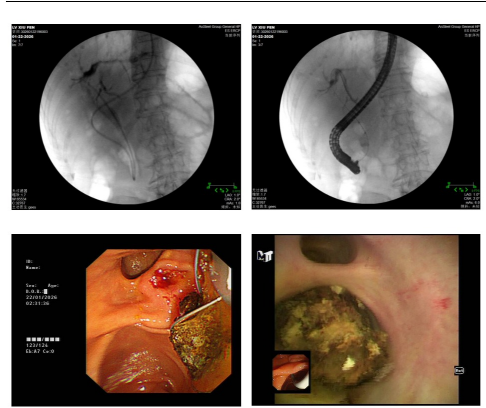

面对如此复杂情况,消化内科团队经过深入讨论与综合研判,最终决定为患者实施经口胆道镜取肝内胆管结石术。该技术属于微创治疗,无需开腹,通过口腔将胆道镜送至胆管内,在直视下精准取石,具有创伤小、恢复快、感染风险低等显著优势,能有效规避腹腔粘连区域,极大降低手术风险。

在消化内科乔强主任的指导下,团队凭借娴熟的微创操作技术,顺利将胆道镜置入患者二级肝内胆管,清晰显露出肝内胆管结石,并将结石完整取出。手术过程顺利,术中无出血。术后患者安返病房。

1. 可视化操作:作为ERCP基础上的“镜中镜”技术,可清晰观察肝内胆管细微结构,解决传统取石视野局限问题,显著降低结石残留率;